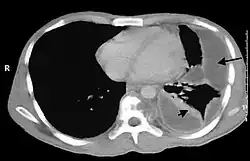

Bei der körperlichen Untersuchung sind ein abgeschwächtes Atemgeräusch bei der Auskultation und ein gedämpfter (hyposonorer) Klopfschall bei der Perkussion über dem Pleuraempyem typisch aber unspezifisch. Für die Diagnose von Pleuraempyemen reicht meist eine konventionelle Röntgenaufnahme des Brustkorbs. Pleuraempyeme sind hier durch eine deutliche Transparenzabnahme gekennzeichnet. Die Eiteransammlung zeigt sich im Röntgenbild in Form einer Spiegelbildung. Bei unklaren Befunden kann eine Computertomographie des Brustkorbs angefertigt werden.